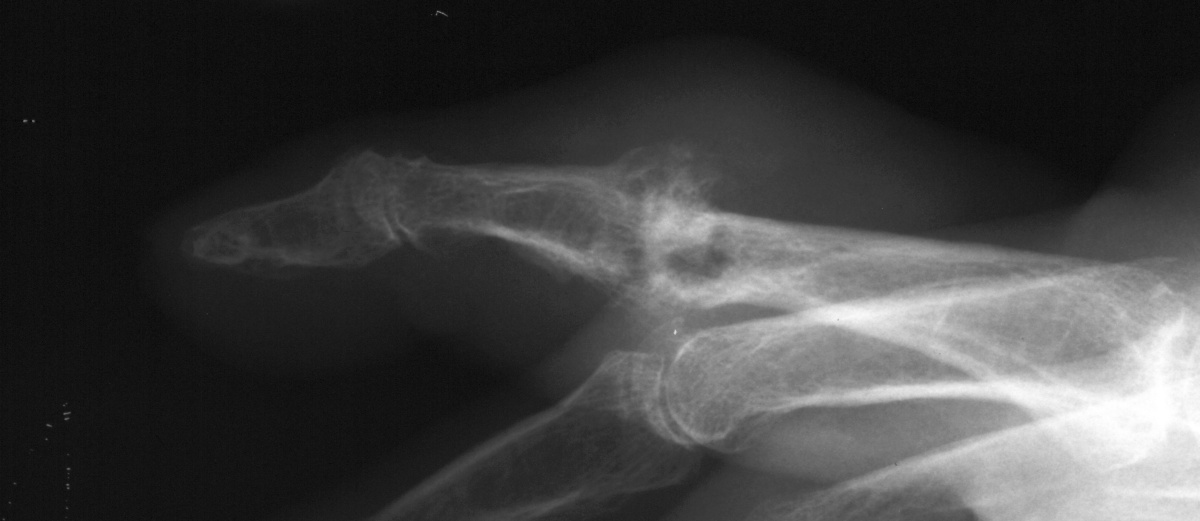

| Case 1. Large tophi have develped

about the right ulnar head and the left ulnar metacarpus, involving the

extensor tendons to the small finger. |